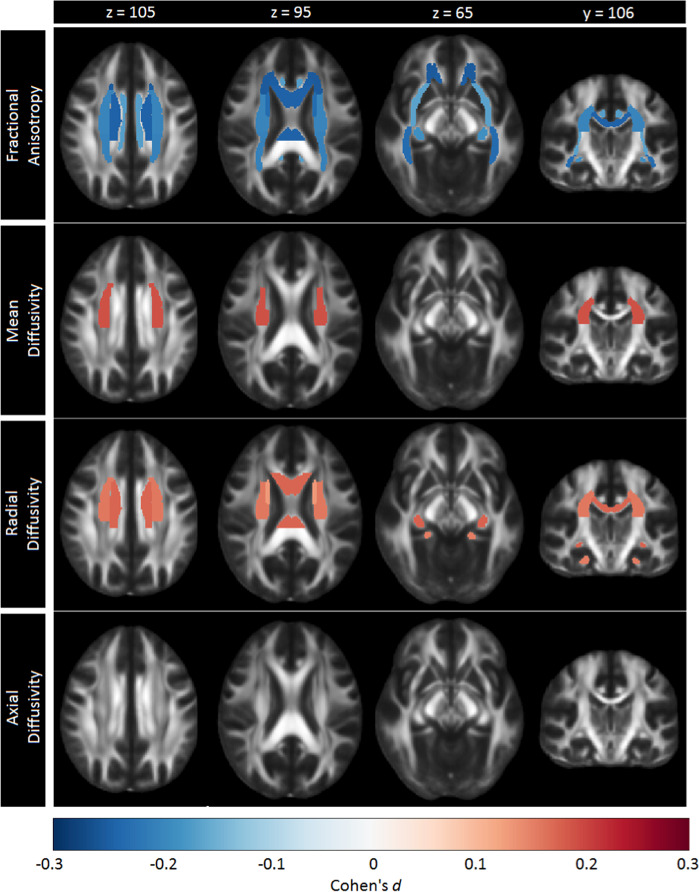

After FDR correction, significantly lower FA was observed for adult MDD patients (N = 921; age range 22–88) compared to healthy controls (N = 1265) in 16 of the 25 ROIs, with the largest effects observed for the full WM skeleton, followed by the anterior corona radiata (ACR), corona radiata (CR), corpus callosum (CC), genu of the corpus callosum (GCC), body of the corpus callosum (BCC) and anterior limb of the internal capsule (ALIC). Significantly lower FA was also observed in the superior fronto-occipital fasciculus (SFO), sagittal stratum (SS), internal capsule (IC), posterior corona radiata (PCR), superior corona radiata (SCR), inferior fronto-occipital fasciculus (IFO), fornix/stria terminalis (FXST), external capsule (EC), and cingulate gyrus of the cingulum bundle (CGC) (Fig. 1, Supplementary Table S4 and Supplementary Fig. 1). No significant effects were observed for AD or MD differences in adults (Tables S4 and S6 and Supplementary Fig. 1). Higher RD for the adult sample was observed across seven ROIs, including the FXST, BCC, SCR, hippocampal part of the cingulum bundle (CGH), the full WM skeleton, CR, and SFO (Fig. 2, Table S7 and Supplementary Fig. 1).

Fig. 1.

Cohen’s d effect sizes for case-control differences in fractional anisotropy, mean diffusivity, radial diffusivity, and axial diffusivity across adults and adolescents

Fig. 2.

Regional overlap in case-control differences in white matter integrity across adults and adolescents

After FDR correction, no significant differences were observed for FA, AD, MD, or RD between adolescent MDD patients (N = 372) and healthy controls (N = 290) (Tables S8–11 and Supplementary Figures. 2 and 3).